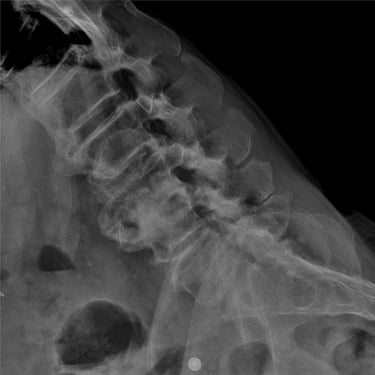

🧠 Fractura Vertebral Lumbar: Estabilización Segura con Fijación Transpedicular (FTP).

La fractura vertebral lumbar genera inestabilidad y dolor severo. La artrodesis con fijación transpedicular es una técnica quirúrgica eficaz que estabiliza la columna, previene desplazamientos vertebrales y mejora la recuperación funcional del paciente.